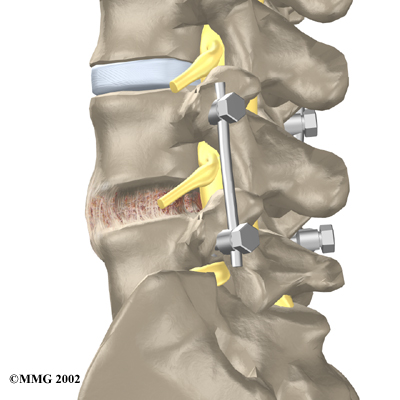

A posterior lumbar fusion may be needed after a surgeon performs a lumbar laminectomy. The fusion procedure is recommended when a spinal segment has become loose or unstable.

A fusion surgery joins two or more bones into one solid bone. This keeps the bones and joints from moving. In this procedure, the surgeon lays small grafts of bone over the back of the spine. Most surgeons also apply metal plates and screws to prevent the two vertebrae from moving. This protects the graft so it can heal better and faster.

Related Document: Active Therapeutic Solutions Guide to Posterior Lumbar Fusion